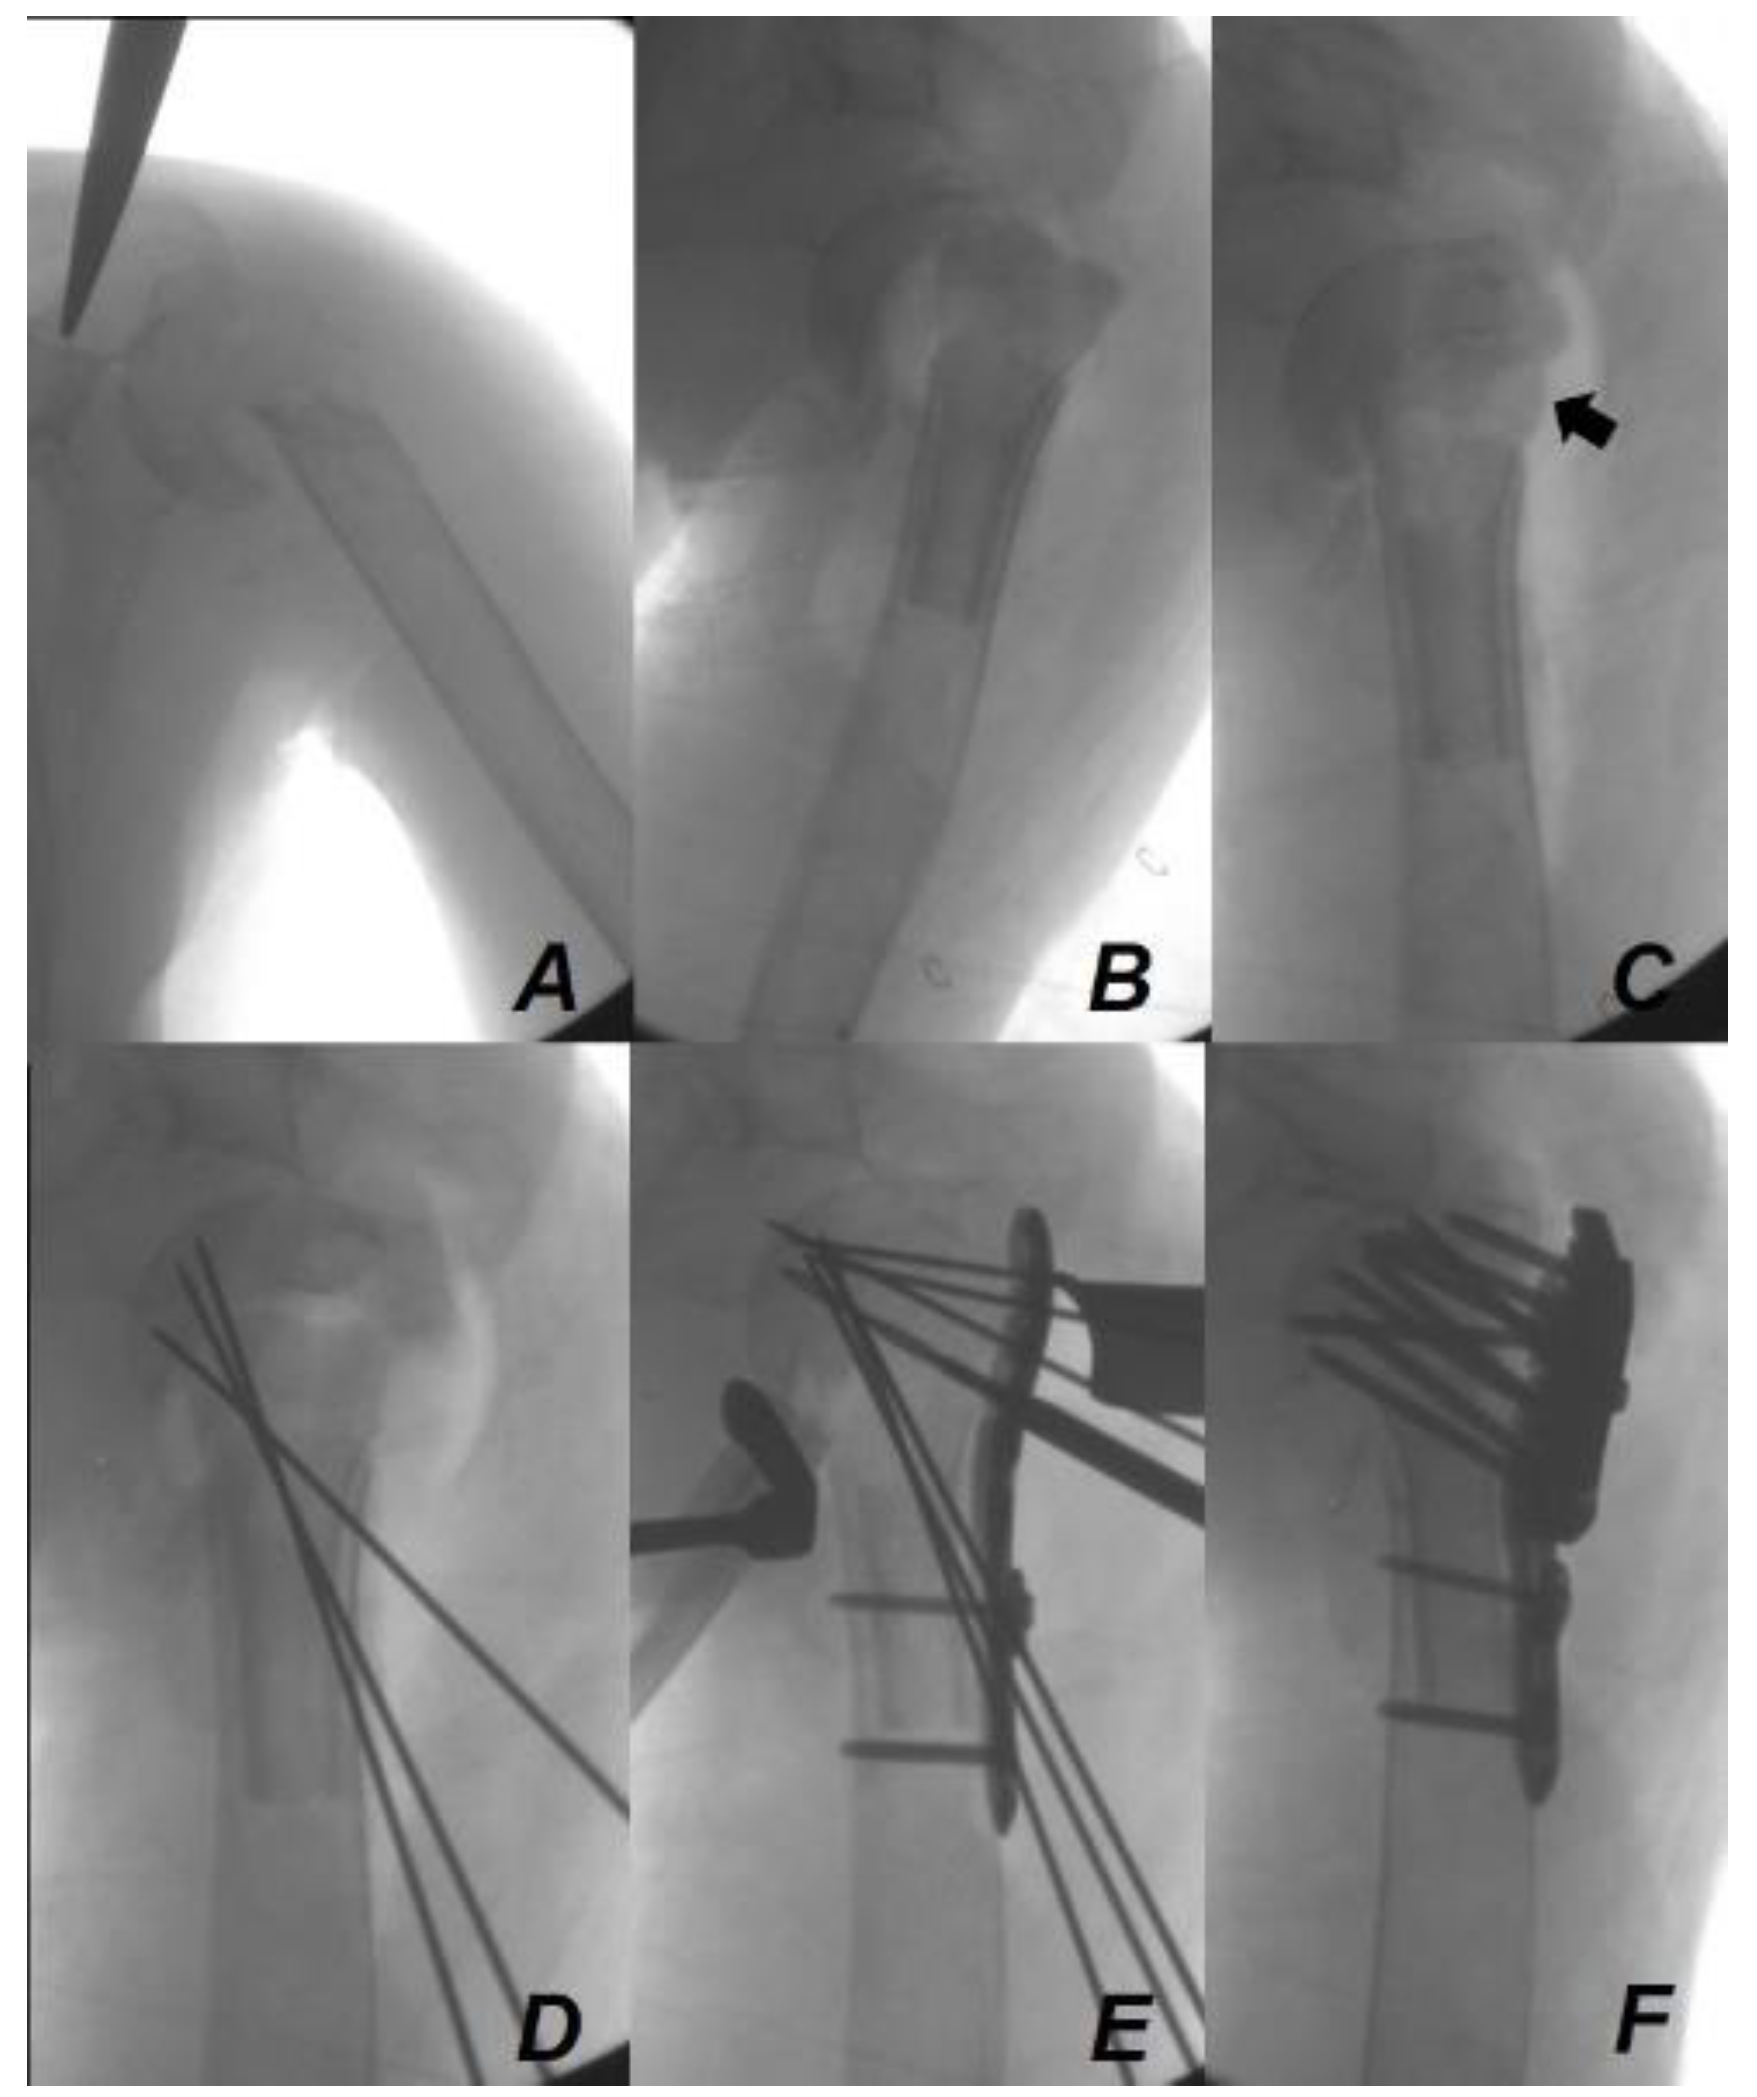

2. Case Presentation

Surgical Technique